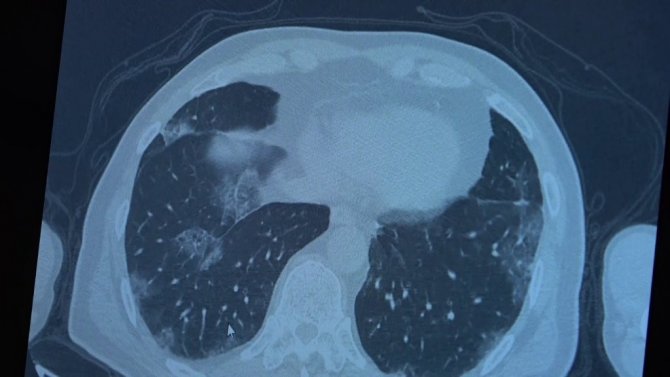

Korona virüs hastalığı genç nüfusta daha fazla görülmeye başlarken Covid-19 aşıları tamamlanan 60 yaş üstü vatandaşlardan bazıları ise korona virüse yakalanmaya devam ediyor. VM Medical Park Samsun Hastanesinde görev yapan Göğüs Hastalıkları Uzmanı Prof. Dr. Şevket Özkaya ise aşının gerçek yaşam sonuçlarını gözler önüne serdi. 2. doz aşıları tamamlanmış fakat Covid-19 servisinde yatan hastaların akciğer tomografilerini inceleyen Prof. Dr. Özkaya, bu kişilerin akciğer tutulumları olduğu halde hastalığı hafif atlattıklarını söyledi.

Bugüne kadar aşının etkilerini hep laboratuvar ortamında antikor üretip üretmemesi ile değerlendirdiklerini belirten Prof. Dr. Özkaya, "Vatandaşlarımız aşılarını olduktan sonra ilk gerçek yaşam sonuçlarını yeni yeni almaya başladık. Gerçekten aşı yaptığımızda antikor oluşturuyor ama bu antikor kişiyi koruyacak mı diye merakla beklediğimiz sorunun cevabını, insanlar 2. doz aşısını olduktan bir ay sonra ortaya çıkmaya başladı. Bu hastalar korona virüsü kaptığında yeni yeni korumaya başladığını anladık. Bir örnek vermem gerekirse, 84 yaşında bir hastamız 2. doz aşısını olduktan sonra eşiyle beraber Covid-19 oluyor. Korona virüsü akciğer tutulumları olduğu halde çok hafif şekilde atlattılar. 65 yaşında başka bir hastamızı göstermek gerekirse, bu hastamız da 2. doz aşısını olmuş ve aradan 1 ay geçtikten sonra antikor da oluşmuş. Bu antikor bu kişiyi koruyacak mı diye gerçek yaşam sonuçlarına baktığımızda, koronanın hastanın akciğerlerine indiği halde çok hafif atlattığını görüyoruz. Eğer bu kişi aşı olmasaydı, hastaneye yatarak daha ağır geçirebilirdi" diye konuştu.

Covid-19 servisinde yatan hastaların yüzde 80'inin gençlerden oluştuğunun altını çizen Prof. Dr. Özkaya, "Artık daha genç hastaların mutant virüsle karşılaştıkları için daha ağır geçirdiği görüyoruz. 60 ve 65 yaş üstünü ise aşıyla sigortaladığımızı düşünüyoruz. Aşının gerçek yaşam sonuçlarının olumlu olduğunu görüyoruz. Aşı olanlar virüse yakalandıkları halde çok hafif veya hastaneye yatmadan atlatıyorlar. Şu an servisimizde yatan hastaların yüzde 80'inini genç hastalar oluşturuyor. Artık 60 yaş üstünde çok fazla hasta görmüyoruz. Örneğin (akciğer filmini gördüğümüz) 40 yaşındaki bir hastamız aşılanmadığı için mutant virüse yakalanmış. Akciğerleri çok kötü durumda ve hastanede yatıyor. 24 yaşında bir genç kızımızda ise ciddi akciğer tutulumları görüyoruz. 49 yaşında bir hastamızı ise maalesef çok ciddi akciğer tutulumu ve neredeyse paramparça bir akciğerle yoğun bakımda takip ediyoruz" şeklinde konuştu.